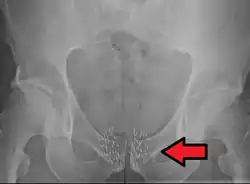

![]() Arrow points to brachytherapy beads used to treat prostate cancer. | |

Brachytherapy to treat prostate cancer can be given either as permanent LDR seed implantation or as temporary HDR brachytherapy.[1]: Ch. 20 [33][34]

Permanent seed implantation is suitable for patients with a localised tumour and good prognosis[33][35][36][37] and has been shown to be a highly effective treatment to prevent the cancer from returning.[35][38] The survival rate is similar to that found with EBRT or surgery (radical prostatectomy), but with fewer side effects such as impotence and incontinence.[39] The procedure can be completed quickly and patients are usually able to go home on the same day of treatment and return to normal activities after one to two days.[6] Permanent seed implantation is often a less invasive treatment option compared to the surgical removal of the prostate.[6]

Permanent brachytherapy, also known as seed implantation, involves placing small LDR radioactive seeds or pellets (about the size of a grain of rice) in the tumour or treatment site and leaving them there permanently to gradually decay. Over a period of weeks or months, the level of radiation emitted by the sources will decline to almost zero. The inactive seeds then remain in the treatment site with no lasting effect.[76] Permanent brachytherapy is most commonly used in the treatment of prostate cancer.[82]